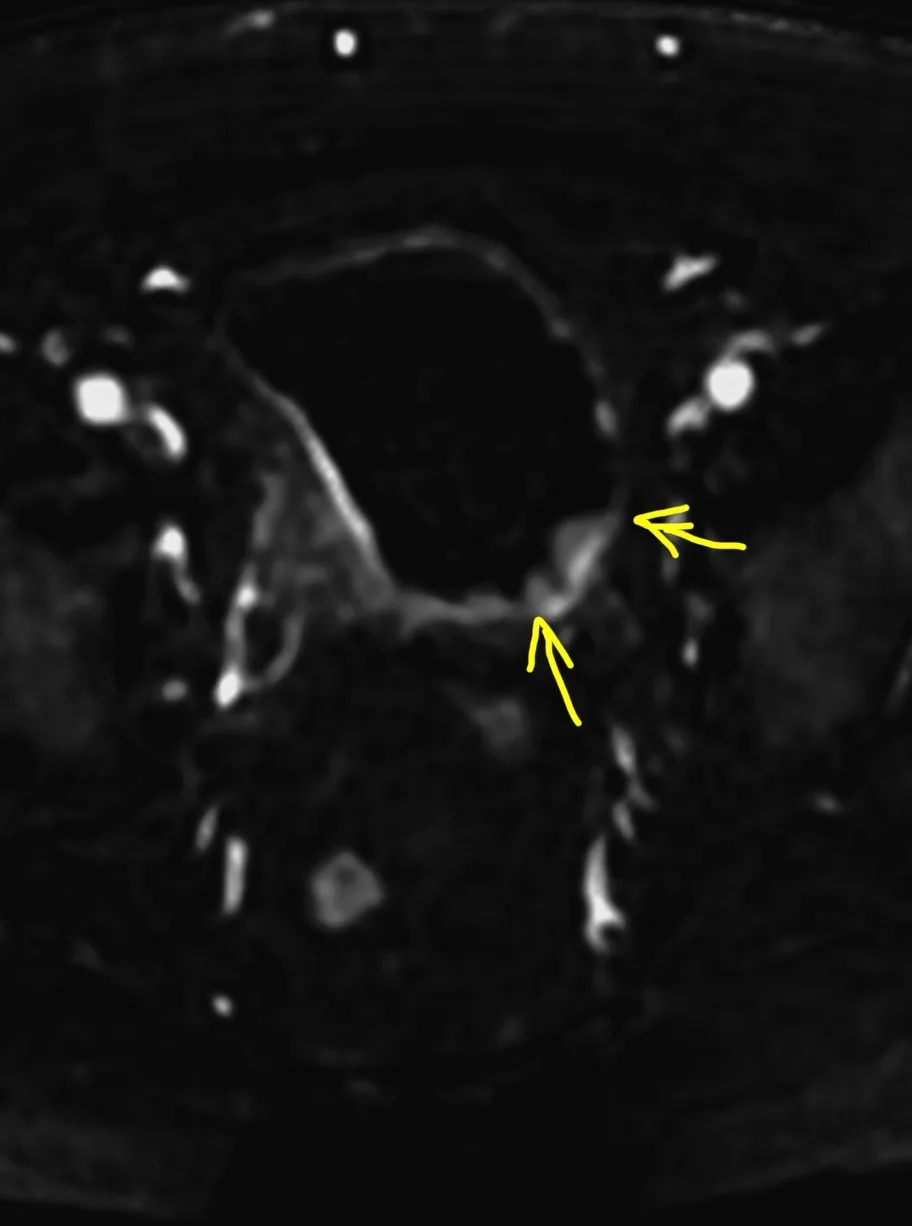

Менингиомы иногда не ходят одни. А по две, три и больше. Самая крупная слева в ЗЧЯ - хорошо видно место, из которого она растет: фокальные утолщения кости по краям и плоское основание опухоли (стрелки).